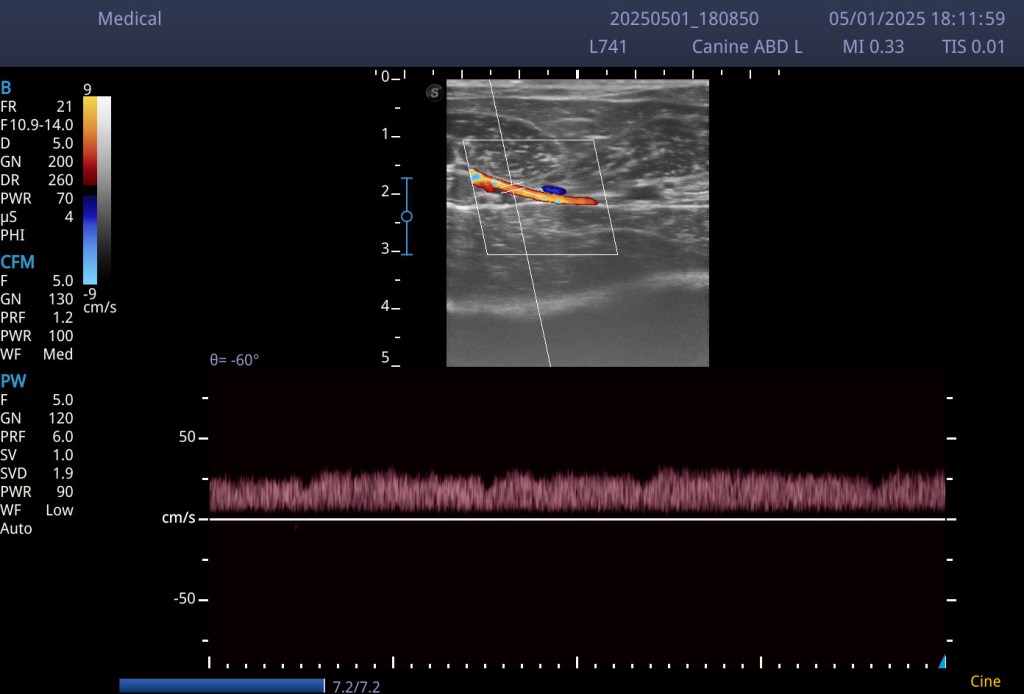

En la imagen que te compartimos hoy, puedes ver una representación muy clara:

- 🔵 Las venas, en cambio, no son pulsátiles (o apenas lo son). Su pared es más fina, colapsan fácilmente con la presión del transductor y el flujo sanguíneo suele ser más lento y continuo.

📸 Imagen educativa:

Vena